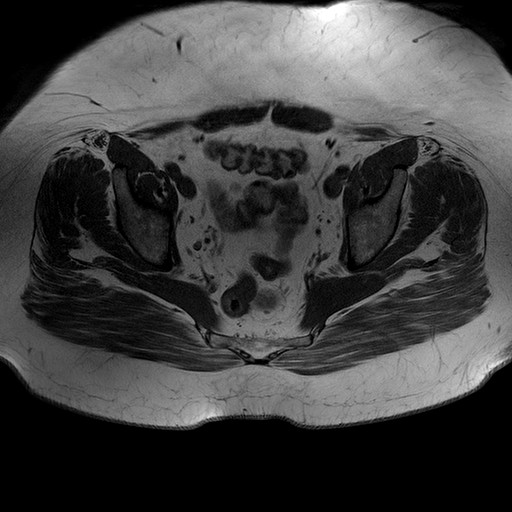

Esami: RMN BACINO

T1W_TSE

Evidenti e simmetriche alterazioni osteofitosiche in regione coxo femorale con riduzione delle rime articolari. Degenerazione completa del cercine glenoideo. Non attuali segni di versamento articolare. Non segni di edema osseo che escludono attuale algodistrofia od osteonecrosi. Lieve e simmetrica riduzione del trofismo della muscolatura glutea.